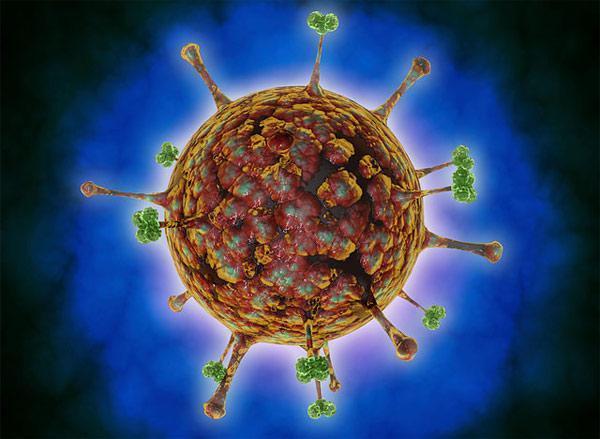

Nipah virüsü ateş, baş ağrısı, boğaz ağrısı ve kaslarda ağrı gibi belirtilerle kendini gösteriyor, gribe benziyor.

Ancak Nipah virüsü bulaşmış bazı insanlarda belirtiler hemen ortaya çıkmıyor.

İlerleyen safhada ise belirtiler baş dönmesi, yorgunluk, bilinç değişikliklerine dönüşebiliyor.

İlk defa Malezya'nın Nipah bölgesinde bir salgınla başlayan virüsün ayrıca biyolojik silah olduğuna dair iddialar da bulunuyor.

En çok Singapur, Malezya, Hindistan ve Bangladeş'te görülen virüs, meyve yarasaları aracılığıyla taşınıyor.